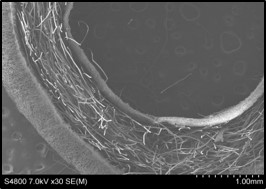

We propose to generate a vascular replacement based on complete reconstitution by using three vascular components (endothelial cells, smooth muscle cells, and pericytes) together with biodegradable scaffolds with topological characteristics similar to native vasculature. We will explore the processes needed to construct the conduit with defined vascular components and we will determine the conditions under which these components can resume function under experimental manipulation. If we are successful, we can produce a novel biologic product that yields a living vascular replacement with responsiveness to environmental stimuli, with potential to grow according to local regulation, and with sufficient mechanical strength and readiness for suturing; these replacements will be nonthrombogenic and self-repairing. If adequate cell sources are located, our proposed process will reduce both the time and the cost of manufacturing. Following GMP regulations, we will be able to make consistently useable products that can be stored as off-the-shelf medical biologicals and used in emergencies.